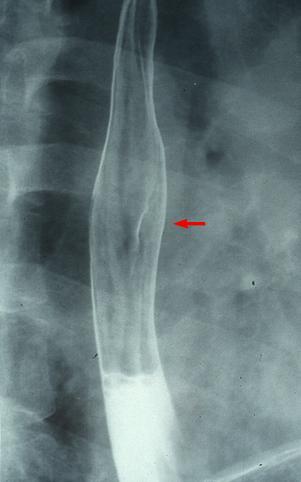

疾患(病理主体)の分類悪性上皮性腫瘍/扁平上皮癌

部位(臓器別)食道/中

検査方法X-P

腫瘍の肉眼分類0型(表在型)/I型(Isp)

病変の最大径(ミリ)15〜19

腫瘍の深達度sm